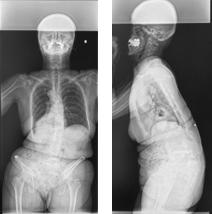

重度脊柱変形に対する矯正固定術

さまざまなお体の病気に伴い、せぼねが重度に変形を起こし息切れなどの症状が出る場合があります。

これらの患者様に対しては状況に応じて、せぼねを矯正固定する場合があります。小児科やリハビリテーション科と相談しながら手術時間や入院期間を検討していきます。